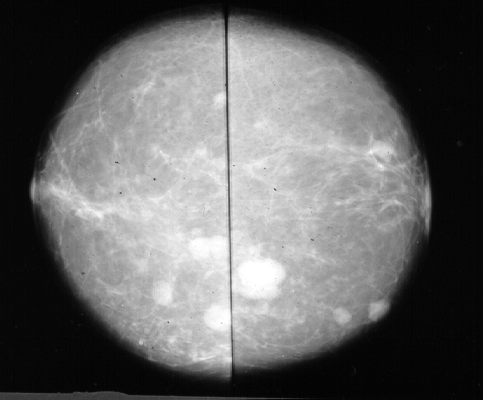

No caso de mamografias é possível identificartumores malignos ou benignos através da análise de sua forma.

Outro objeto em pleno desenvolvimento é um banco de mamografias.

Este conjunto de imagens digitalizadas de mamografias resulta de colaboraçãoentre o Instituto de Computação e Radiologia da UniversidadeFederal Fluminense.

O principal objetivo da disponibilização destas imagense facilitar pesquisas e desenvolvimentos ligados a mamografias de rotina.

Também pretende-se auxiliar o desenvolvimento de algoritmos deprocessamento de imagens e servir a propósitos de ensino, treinamento.

As mamografias sao de pacientes diversos e contem tanto tumores diagnosticadoscomo benignos quanto malignos.

Cada imagem foi previamente diagnosticada pelos Departamento de Radiologiada UFF, Hospital Universitario Pedro Hernesto e pelo IRSA-Instituto deRadiologia s.a.